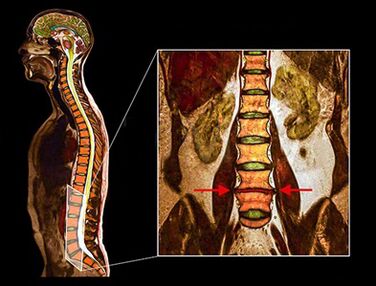

- MRI: This diagnostic method allows you to clarify the degree of degeneration, the presence of fractures, stenosis discs.Often, a magnetic resonance study is necessary in preparation for surgical treatment to accurately determine the location of the degenerate disc and plan the operation.

Studies have shown that the results of magnetic resonance with degeneration of moderate or significant disks are found when exploring patients, both with at least severe pain or lack of pain.In addition, many painful conditions may not appear in a magnetic resonance.For this reason, the diagnosis cannot be done exclusively on the basis of the results of the visualization, and the verification of the diagnosis is possible only on the basis of all the methods of clinical and instrumental examination.